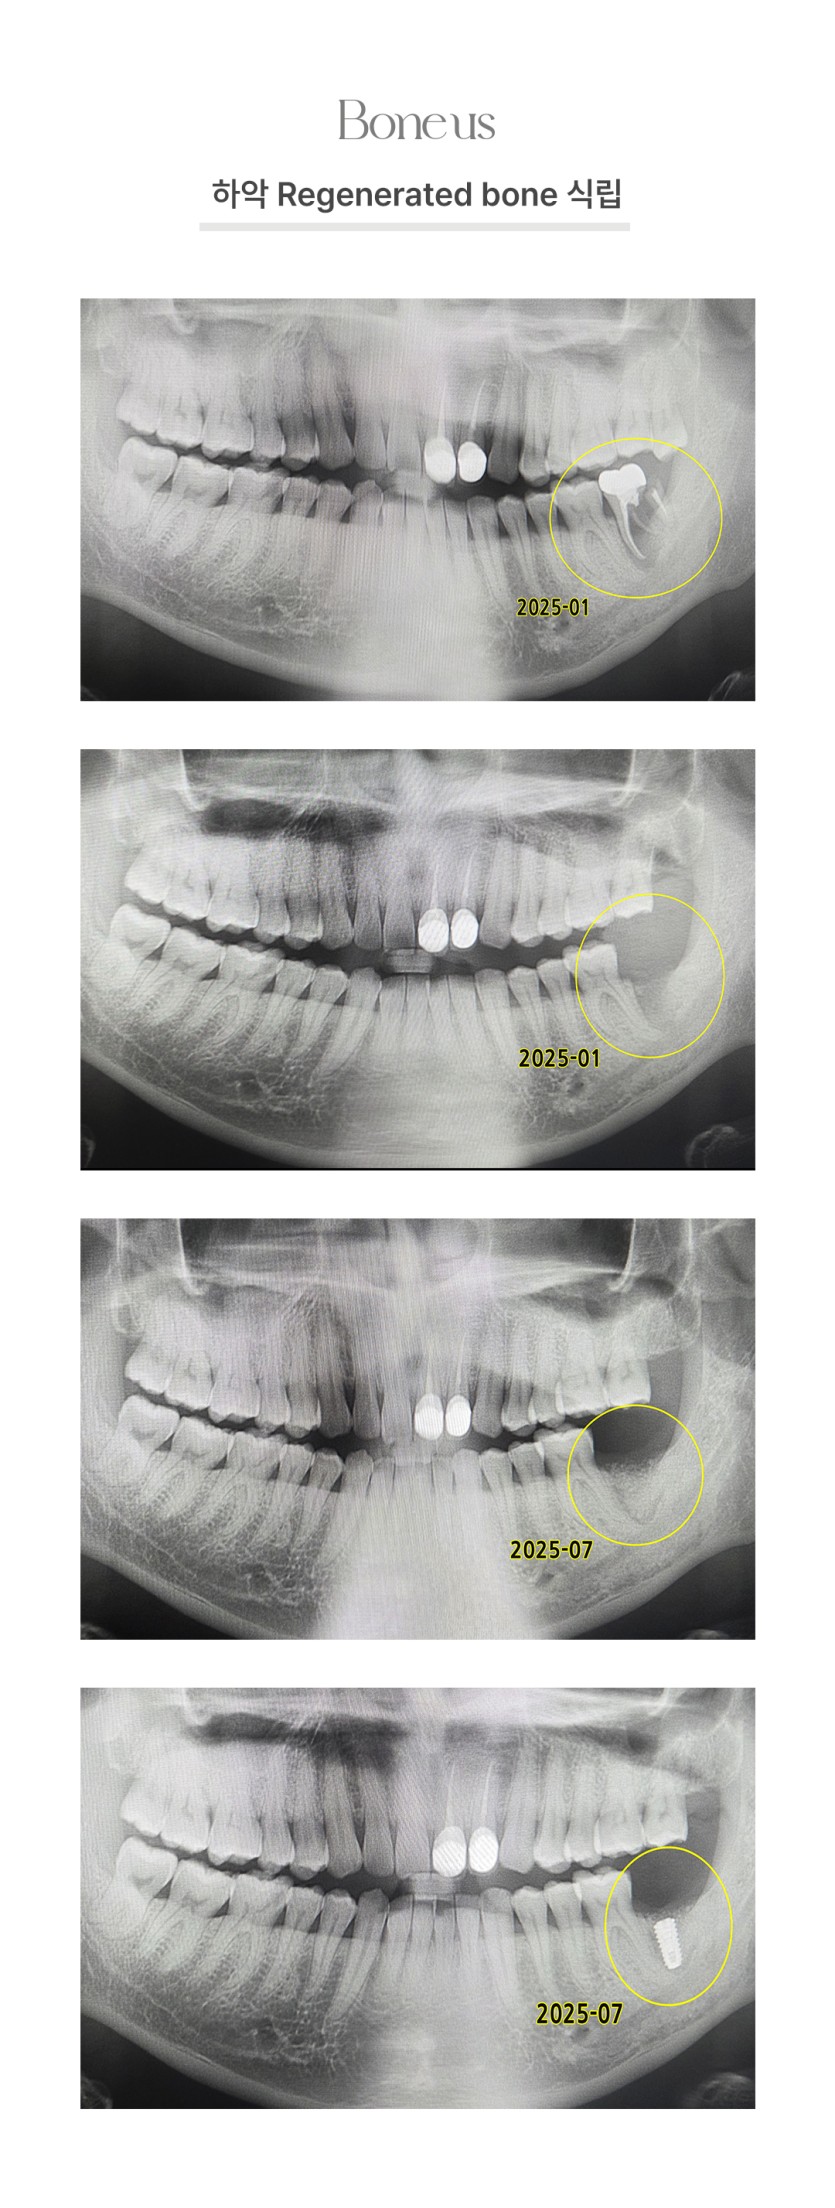

CLINICAL CASE

본어스 시술사례

하악 Regenerated bone 식립 2

하악 Regenerated bone 식립 1